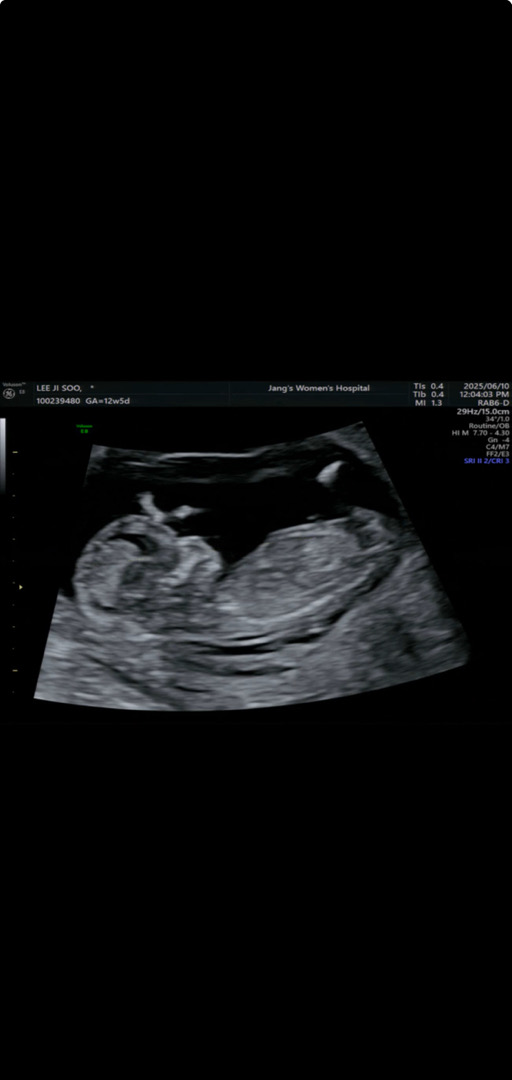

13주 1일차 아가 성별 알 수 있을까용?

각도법 고수님들께 조심스럽세 여쭤봅니당!!

딸 각도 같아요

아들일거같아용

전 딸에한표요

아들